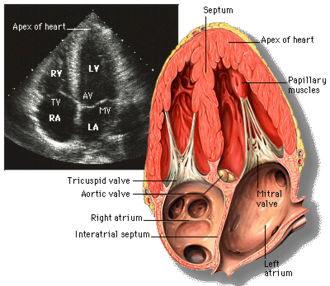

Cardiac phantom with myocardium, chambers, valves, and coronary arteries

AI-generated comprehensive cardiac phantom with all four chambers, valves, coronary arteries, great vessels,...